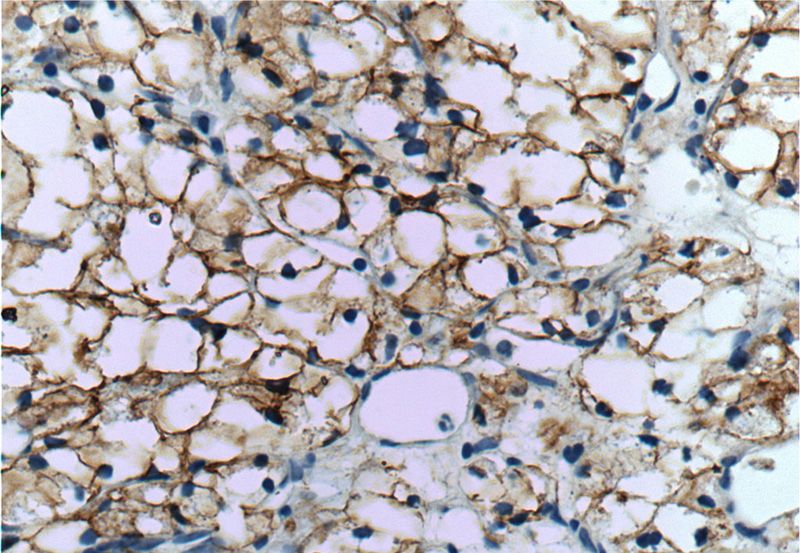

Immunohistochemistry of paraffin-embedded human renal cell carcinoma tissue slide using Catalog No:108740(CA9 Antibody) at dilution of 1:50 (under 40x lens)